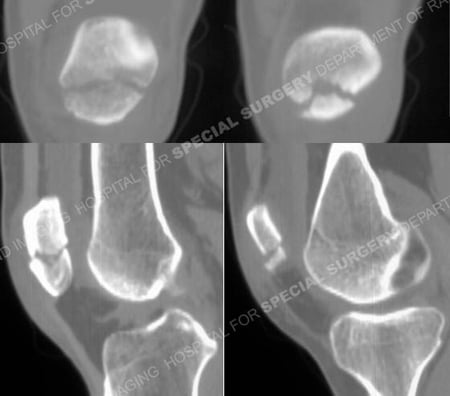

CT scan images